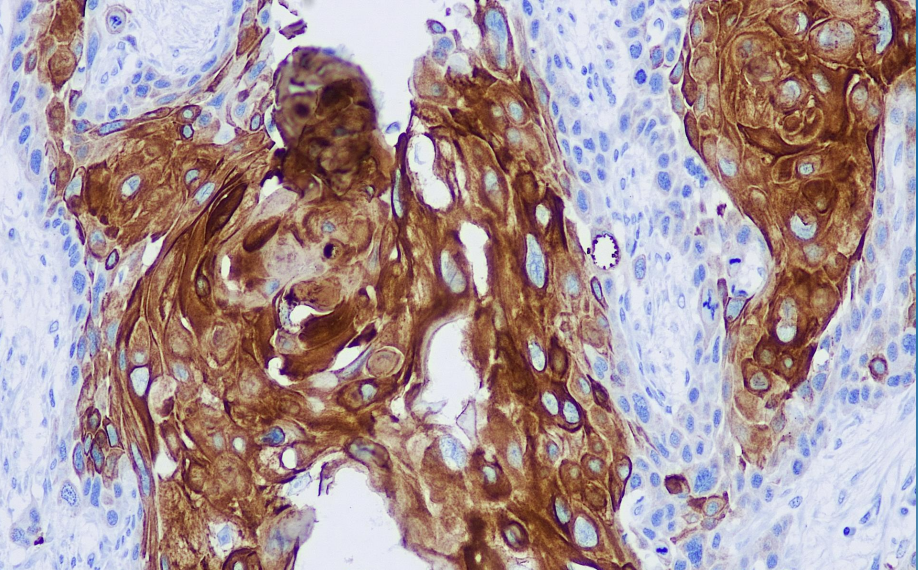

Positive control: Esophageal squamous carcinoma

This antibody recognizes cytokeratin with a molecular weight of 46 kD and is positive in normal tissues for basal cells of complex epithelia, basal cells of tracheal/laryngeal/bronchial pseudocomplex epithelial cells, and meibomian epithelial cells of salivary glands; in tumor tissues, this antibody recognizes squamous cell carcinomas, primarily of the lungs, uterine cervix, and oral cavity.

CK16 antibody reagents can specifically bind to CK16 molecular antigens. Immunohistochemistry kits containing CK16 antibody reagents are suitable for the auxiliary diagnosis of squamous cell carcinoma.